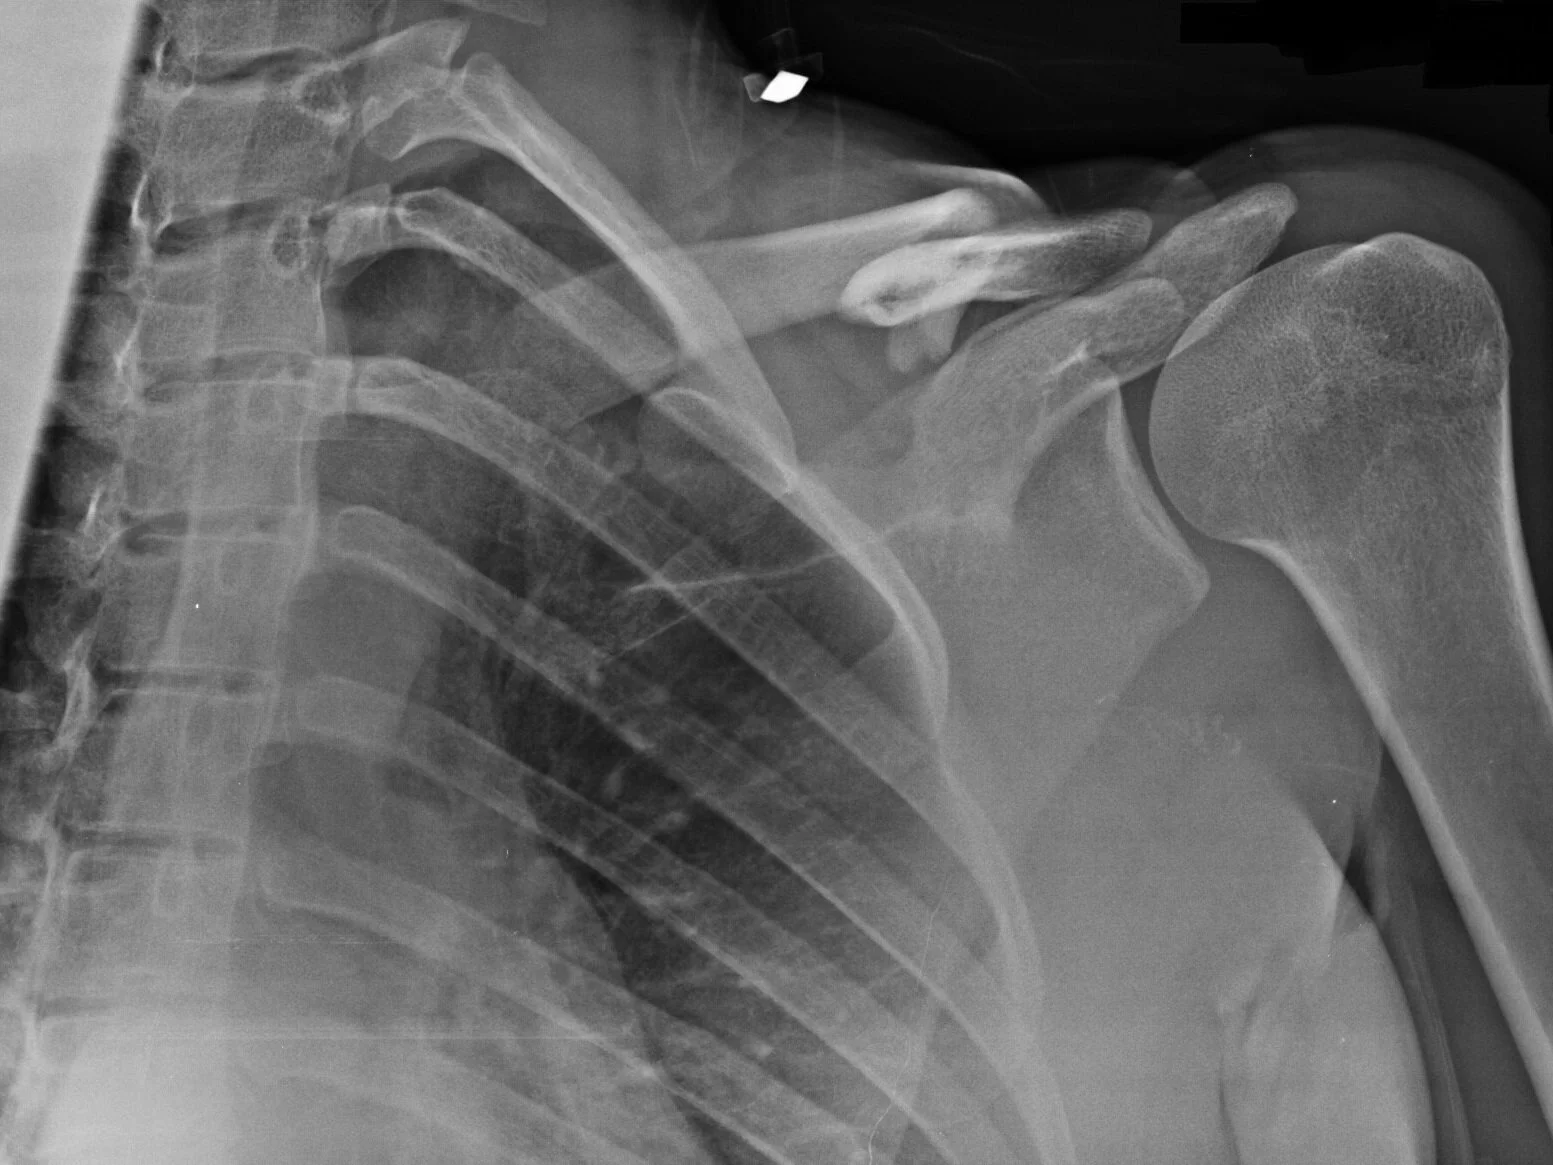

La diagnosi è innanzitutto clinica dopo esame visivo, palpatorio e funzionale della spalla. A completamento diagnostico una radiografia evidenzierà la morfologia della frattura. Nelle fratture pluriframmentarie può essere indicata l’esecuzione di una TAC per una migliore pianificazione preoperatoria.

La clavicola è l’osso che collega lo sterno alla scapola ed oltre ad essere il fulcro per tutti i movimenti della spalla, protegge vasi e nervi dell’arto superiore. La frattura di clavicola è una lesione molto comune che si verifica soprattutto negli atleti che praticano sport da contatto (rugby) oppure sport a rischio caduta (motociclismo, ciclismo, sci) ma può verificarsi anche nelle persone comuni in seguito ad una caduta e trauma diretto sulla spalla o indiretto sul gomito o sulla mano protesa a difesa).